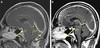

QUAL O DIAGNÓSTICO?

HIPOTENSÃO LIQUORICA A) Coleção de LCR reteoespinhal B) Vazamento periradicular C e D) Coleção epidural